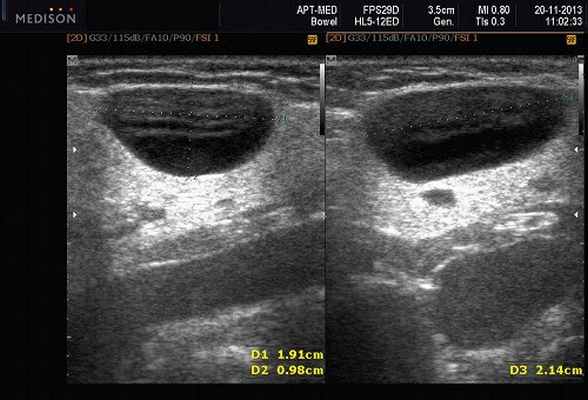

- обструктивные сиаладениты, развивающиеся при затруднении оттока слюны при обструкции выводного протока камнем (рис. 5-7) или сгустившимся секретом, а также вследствие рубцового стеноза протока. По распространенности процесса различают очаговый, диффузный сиаладениты и сиалодохит - воспаление выводного протока. Течение процесса может быть острым и хроническим;

Рис. 5. Камень протока поднижнечелюстной слюнной железы.

Рис. 6. Камень в паренхиме поднижнечелюстной слюнной железы.

Рис. 7. Камень в протоке поднижнечелюстной слюнной железы.